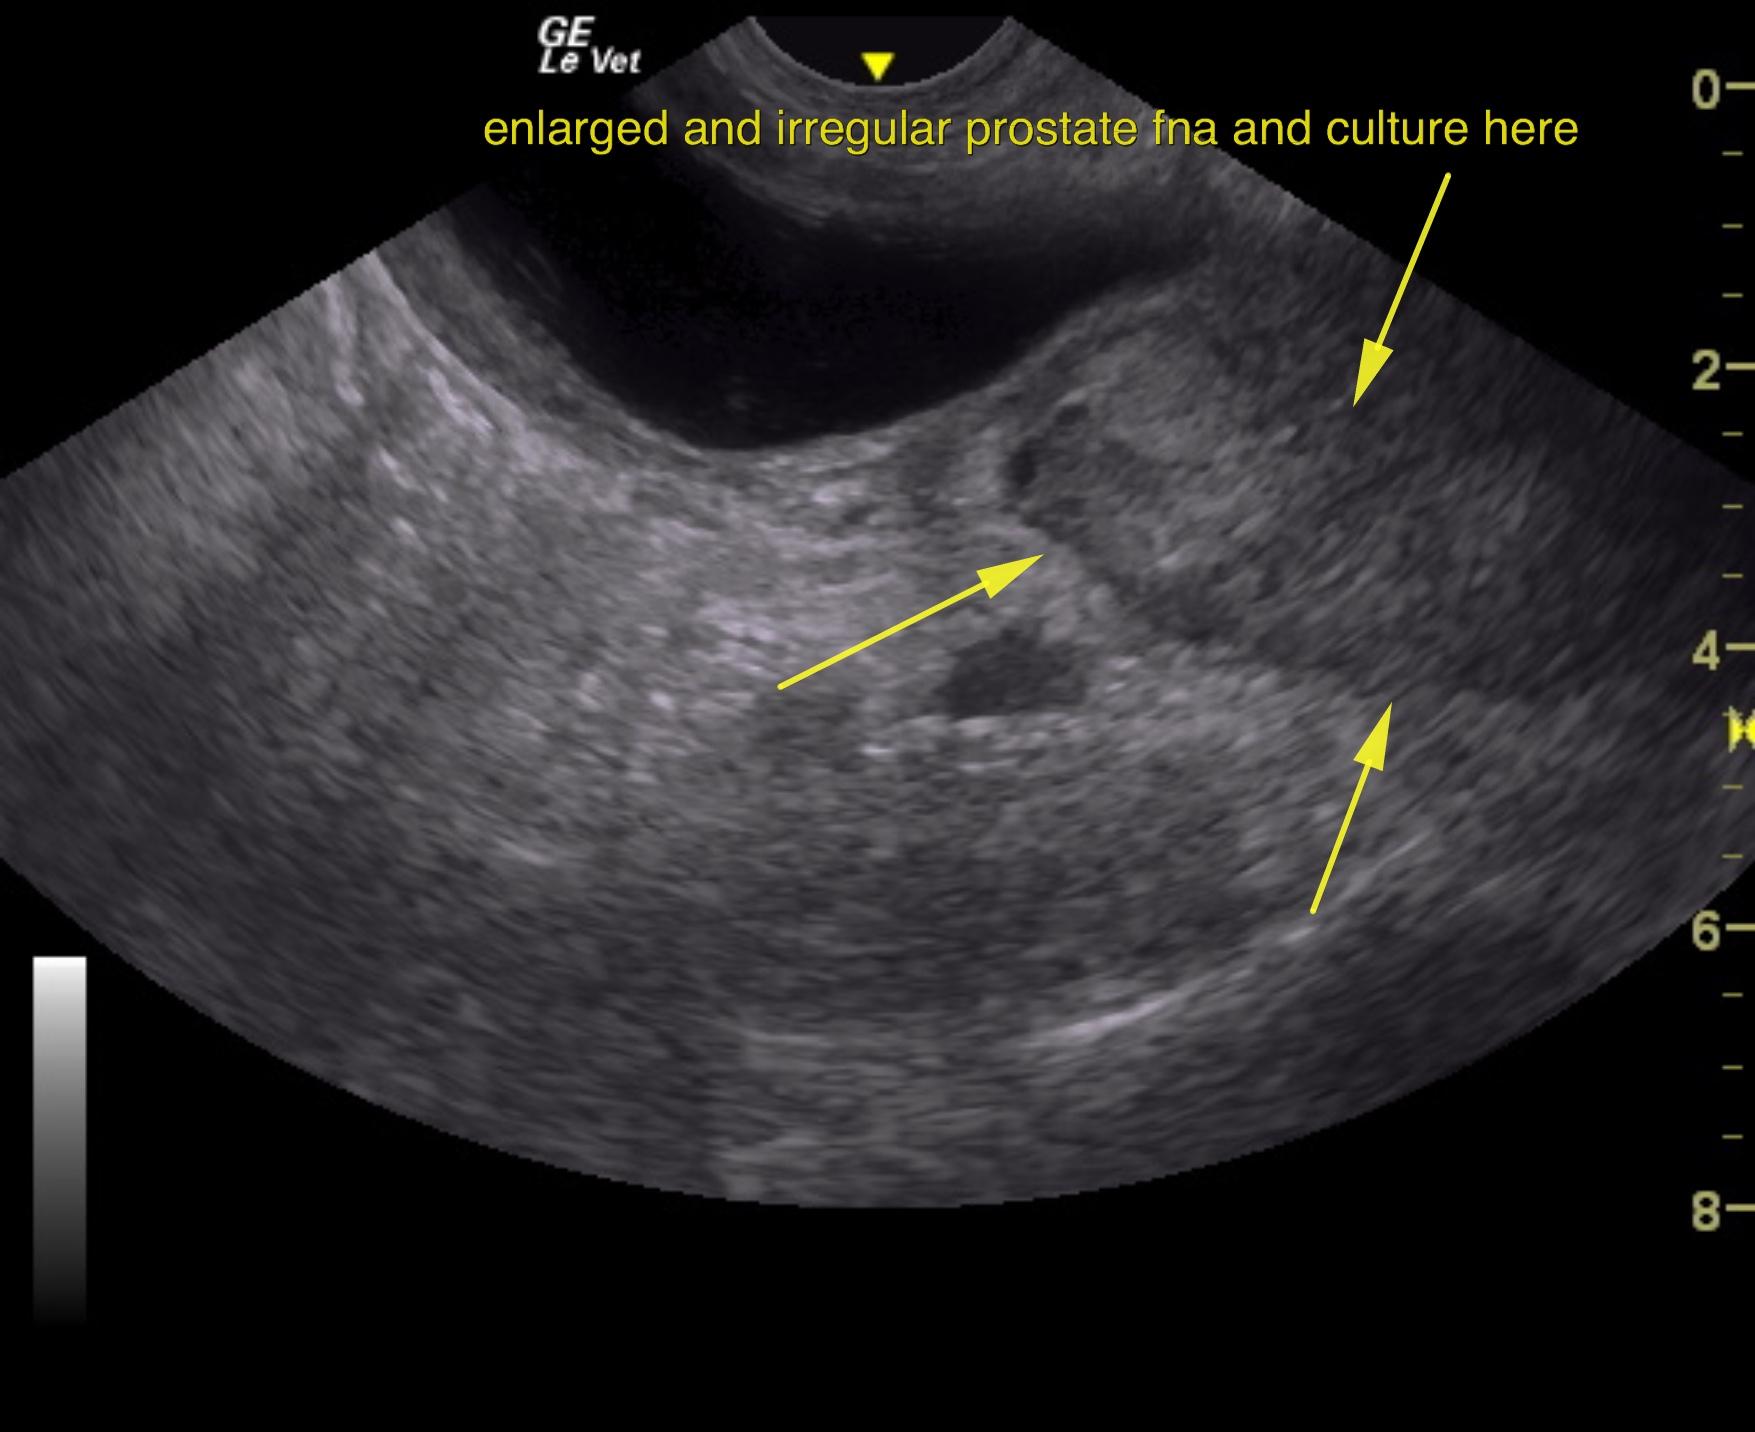

An 11-year-old NM Labrador with a history of gradual weight loss was presented for evaluation of abdominal pain and diarrhea. On abdominal palpation, the intestines were gas-filled, which was confirmed on survey radiographs. Elevated ALT activity, BUN, and glucose were present on serum biochemistry.